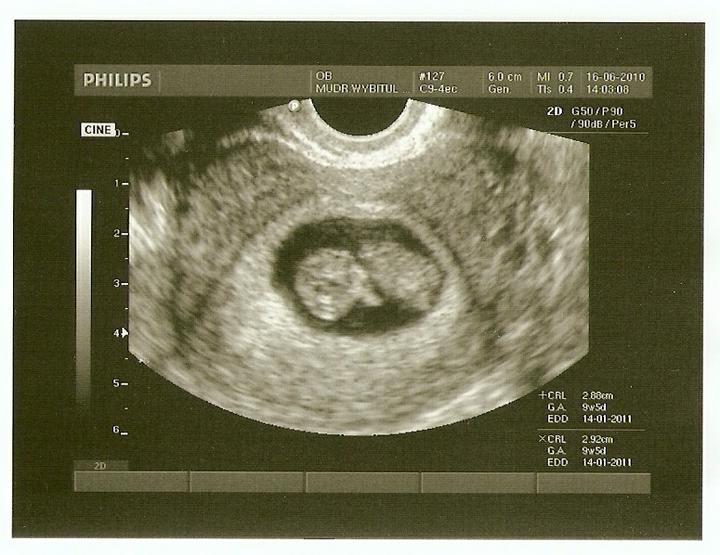

Těhotenský test v IVF

Domácí těhotenský test se obvykle doporučuje udělat nejméně 10 dnů po poslední dávce Pregnylu. Záleží tedy na tom, zda při punkci vaječníků byl získán nižší počet oocytů, a proto byly aplikovány ještě 1 až 3 menší dávky Pregnylu nebo zda byl získán větší počet oocytů a Pregnyl se aplikoval pouze před punkcí.

- možnost zachycení biochemického těhotenství, které neprosperuje. Je poměrně běžné, u přirozeného cyklu se děje také často - žena ani neví, že je těhotná, jen se jí případně mírně opozdí menstruace. Tento termín označuje situaci, kdy dojde k uhnízdění embrya, které však bylo slabé nebo nekvalitní a po čase se rozpadá. Vzhledem k tomu, že po IVF má většina žen tendenci testovat příliš brzy a velmi citlivým testem, takovéto těhotenství se může zachytit. Je to ale ještě také příliš brzo, aby těhotenství bylo možné potvrdit na ultrazvuku. Označuje se tedy jako "biochemické", protože je zjištěno pouze testem z moči, případně z krve (narozdíl od zamlklého těhotenství, které bylo již prokázáno nálezem na ultrazvuku). U testu z krve se obvykle vyskytují nízké hodnoty, které při opakovém provedení klesají.